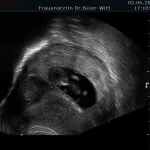

Frühschwangerschaft:

Ultraschall_5